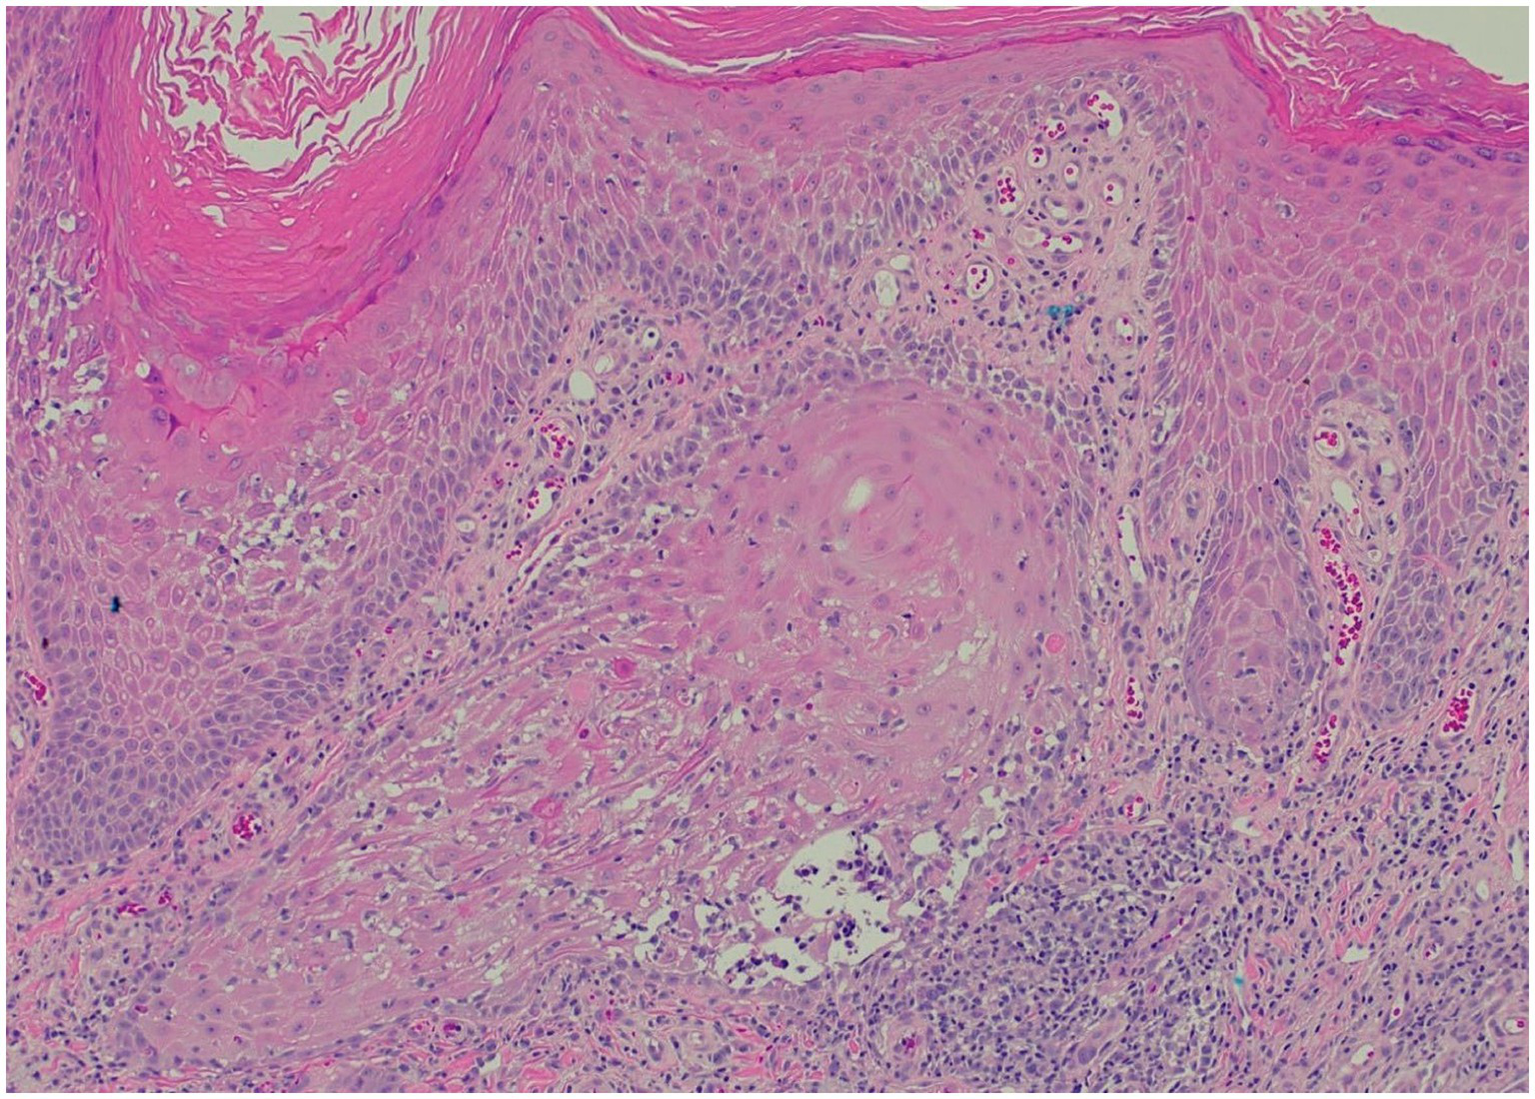

Clinically, HLP plaques are frequently located on the distal lower extremities and are associated with follicular accentuation (4, 5). Additionally, patients may have no history of sun damage and no predisposing risk factors for cSCC (13). Histologically, HLP is notable for hyperorthokeratosis, wedge-shaped hypergranulosis, and irregular psoriasiform hyperplasia limited to the epidermis (Figure 3), while cSCC presents with cytologic atypia, extension beyond the superficial dermis, and other invasive characteristics (6, 13).

Figure 3

Representative histopathological image for our patients (H&E stain): saw-toothed rete ridges and a band-like lymphohistiocytic infiltrate at the dermoepidermal junction, along with wedge-shaped hypergranulosis and civatte bodies.